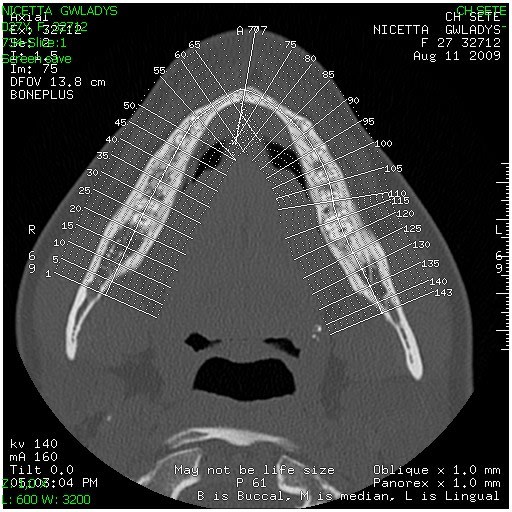

Etonnant que personne ne réagisse mais il y a d'autres moyens prothétiques pour restaurer ce genre de défaut. Les implants ne sont pas une solution à tous les problèmes.

Si la patiente dans ton cas refuse la greffe alors pour moi ce n'est pas un bon candidat pour l'implanto. 27 ans, crête extra fine, ....

Je te poste un cas de bridge collé antérieur 32-42 qui peut être parfaitement intégré dans le contexte gingival si ton prothésiste s'en donne l'effort.